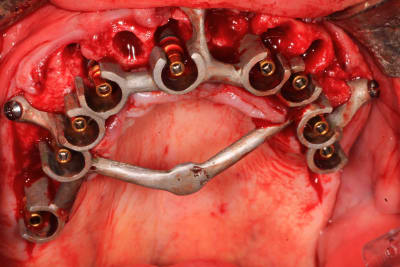

En effet le titane coulé c'est très compliqué, j'ai coulé le guide que présente jeff (23) en Cobalt-chrome

non, le chrome cobalt est très résistant, je n'ai jamais eu de casse avec mes guides ajourés. Ils offrent une bonne visibilité contrairement au guide à étage en plastique comme tu peux l'observer avec celui de jeff.

Voici Prunelles Les bridges (24) que jeff a posé en fin d"intervention. Maintenant que le protocole est bien rodé en consacrant une journée de 3 à 6h pour 1 ou 2 maxillaires ça rentre vraiment dans le sentiment d'un exercice quotidien.